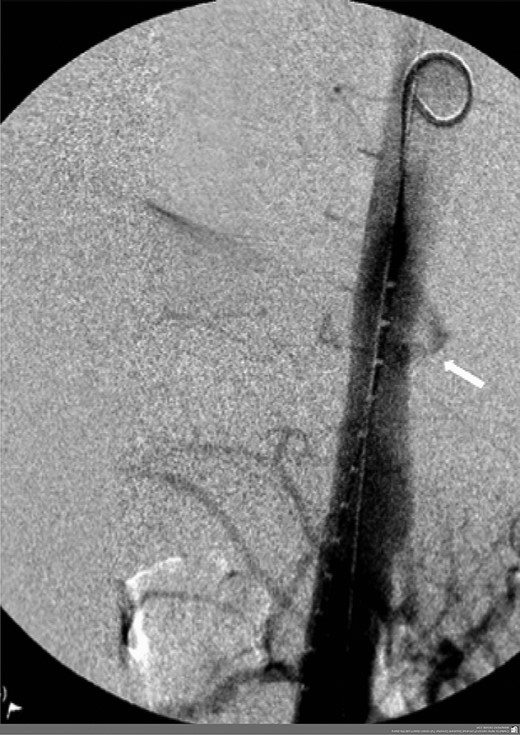

However, 4 and a half months later he again became haemodynamically unstable with a further episode of haematemesis. A further CT angiogram showed contrast entering the neo-oesophagus from the thoracic aorta (Fig. 5). The patient was again taken to the emergency theatre and the previous stent was relined with further stents extending both proximally and distally beyond the previous stent, with care taken not to occlude the celiac trunk and arteries below this (Cook Medical ZTA-26-105 and Cook Medical ZTA-28-109). Again, the patient had a quick recovery. However, repeat endoscopy showed that the aortic stent was visible through a defect in the wall of the neo-oesophagus (Fig. 6).

Second admission: CT angiogram showing aorta-enteric fistula demonstrated by arrow (axial and sagittal view, respectively).